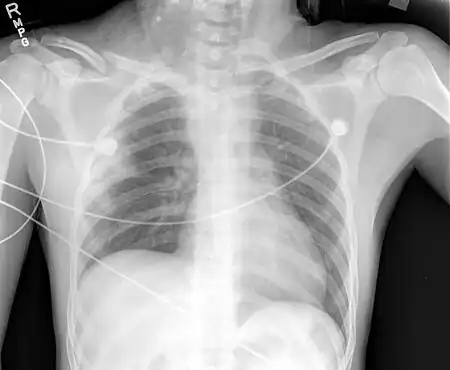

A brachial plexus injury (BPI), also known as brachial plexus lesion[1], is an injury to the brachial plexus, the network of nerves that conducts signals from the spinal cord to the shoulder, arm and hand. These nerves originate in the fifth, sixth, seventh and eighth cervical (C5–C8), and first thoracic (T1) spinal nerves, and innervate the muscles and skin of the chest, shoulder, arm and hand.[2][3][4]